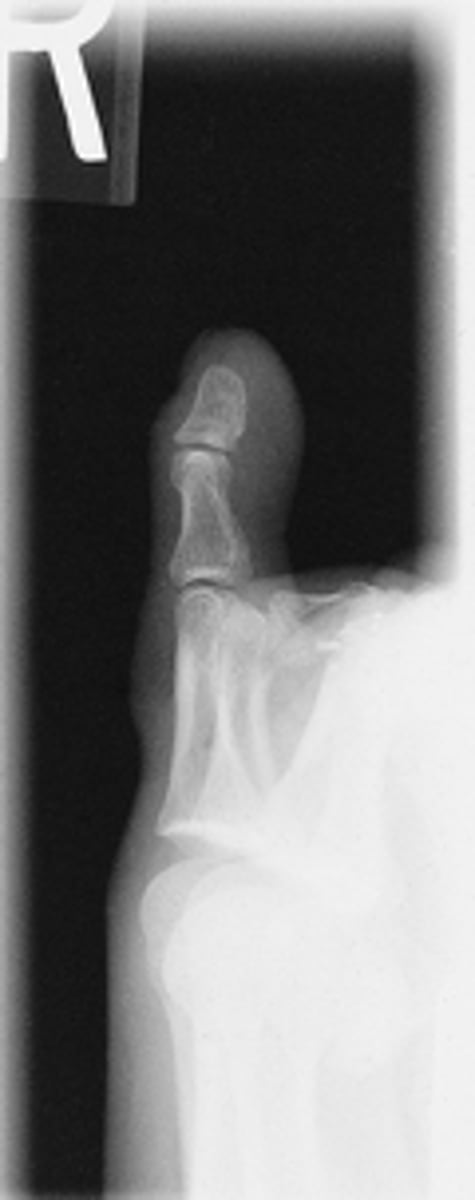

Lateral Fourth Digit

What projection is this?

Evaluation Criteria for

- CR to PIP

- Mediolateral

- Digits presented in true lateral position

- IP and MTP joints appear open

- Digit free of superimposition

- Optimal exposure factors